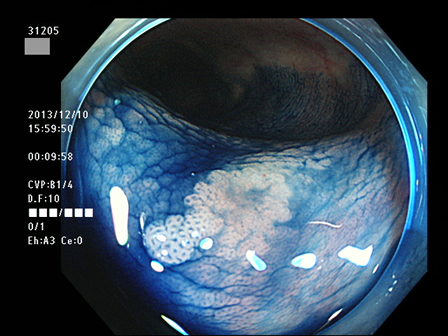

上記100名より抽出した平坦・陥凹型腺腫(=癌化の危険が高いが見落としやすい病変)の内視鏡写真

腺腫発見率 60% (カルテ番号31200〜31299の100名の方の検査結果で集計)

以下のカルテ番号の方に腺腫(Adenoma,Group3〜5)が見つかりました

31201 31203 31205 31206 31207 31208 31211 31212 31213 31214 31216 31217